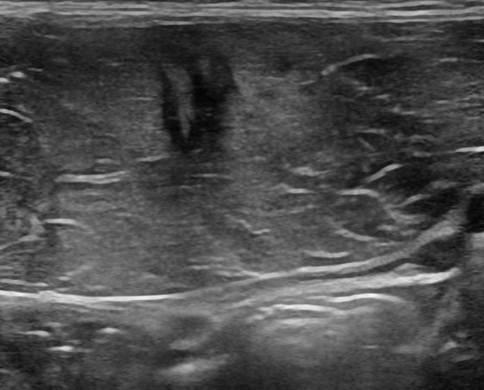

Chấn thương thành bụng

» Thông tin: Nam giới – 18 tuổi.

» Lâm sàng: Chấn thương thành bụng.

# Đụng dập, tụ máu cơ thành bụng.